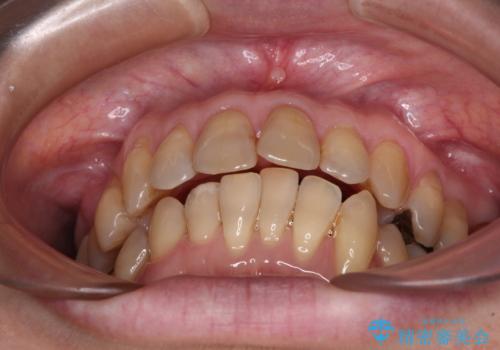

- 上下前歯のデコボコと、奥歯の銀歯を気にして来院された患者様です。

仕事柄あまり目立つ装置は付けることは避けたいとのことで、インビザラインによるマウスピース矯正を行うこととしました。

概ね歯列が整ったところで銀歯の全てをセラミッククラウンなどに置き換え、その後インビザラインを1セット使用して仕上げていくこととしました。

矯正治療の後半にはホワイトニングもされ、スッキリした口元に仕上げることができました。